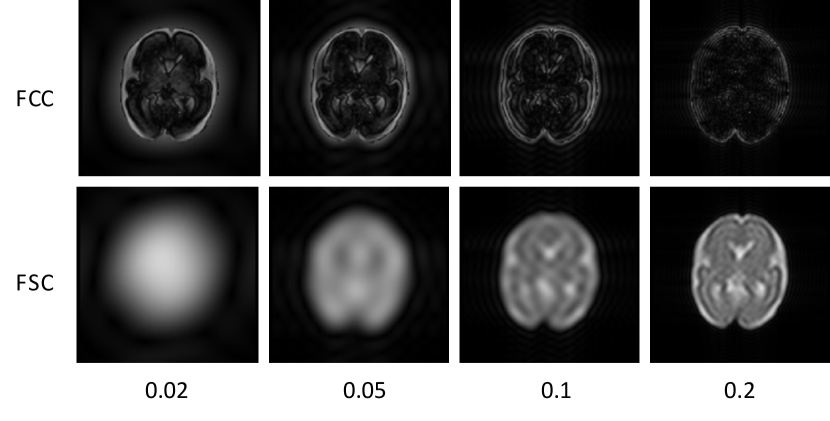

4.5 Component of the Fourier Code

In the Fourier code described in Section 3.2, the hyperparameter α𝛼\alpha plays a crucial role in determining the information of FCC and FSC. To investigate the impact of α𝛼\alpha, we set α𝛼\alpha to 0.02, 0.05, 0.1, and 0.2, respectively. As illustrated in Fig. 9, a smaller α𝛼\alpha provides a clearer FCC and a more blurry FSC, and vice versa. However, since the generator relies on the FSC to generate realistic synthetic images, it is crucial that the FCC and FSC reach a balance between texture/structure and domain-invariant information. Therefore, choosing an appropriate α𝛼\alpha is essential for achieving optimal performance. In our experiments, we found that the best results are obtained with α=0.05𝛼0.05\alpha=0.05, which thus serves as a default setting in our method.

Refer to caption

Figure 9: Visualization of FCC and FSC under different α𝛼\alpha values.

Table 4: Segmentation performance of our method under different α𝛼\alpha.

α𝛼\alpha Dice [%] \uparrow

CSF GM WM Ven. Cer. Bra. Mean

0.02 86.7±2.8 72.6±4.5 88.7±3.4 82.1±6.6 84.5±11.7 76.8±7.4 81.9±3.1

0.05 89.9±2.2 74.1±2.7 90.5±1.3 83.4±5.5 88.9±4.8 78.9±7.1 84.3±2.1

0.1 90.5±2.0 73.4±3.4 89.8±1.7 83.5±4.8 87.7±5.2 78.4±7.4 83.9±1.8

0.2 88.2±1.6 68.5±4.0 88.0±3.2 80.5±3.0 85.8±4.7 78.9±4.0 81.7±1.8